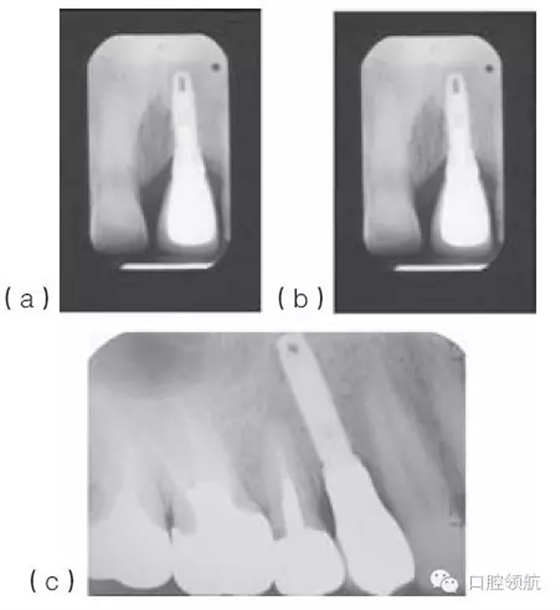

種植體適當(dāng)?shù)那蓄i/ 頸向位置,有利于建立逐漸過(guò)渡的外形和正常的穿齦形態(tài)。種植體切頸/牙合頸向的定位,很大程度上取決于現(xiàn)存骨的位置(圖10.33a~c),以及滿足美學(xué)需求的頸部過(guò)渡形態(tài)。因?yàn)榉N植體的平臺(tái)接口為小直徑的圓形,而齦緣的修復(fù)體截面為直徑較大的不規(guī)則幾何形態(tài),中間需要一定的過(guò)渡才能滿足美學(xué)的需求。一般來(lái)說(shuō),種植體植入到鄰牙釉牙骨質(zhì)界稍下方,以使所需的形態(tài)學(xué)改變逐步發(fā)生(圖10.34)。

圖10.33 (a)金屬烤瓷冠粘結(jié)后的根尖片。(b)種植體位于鄰牙釉牙骨質(zhì)界根方3mm的根尖片。切嵴到種植體頂部的距離太大,導(dǎo)致種植體金屬部件可能承受較大的力。(c)種植體植入到嚴(yán)重骨吸收的上頜第一前磨牙區(qū)。種植體到面的距離幾乎等于種植體的長(zhǎng)度。